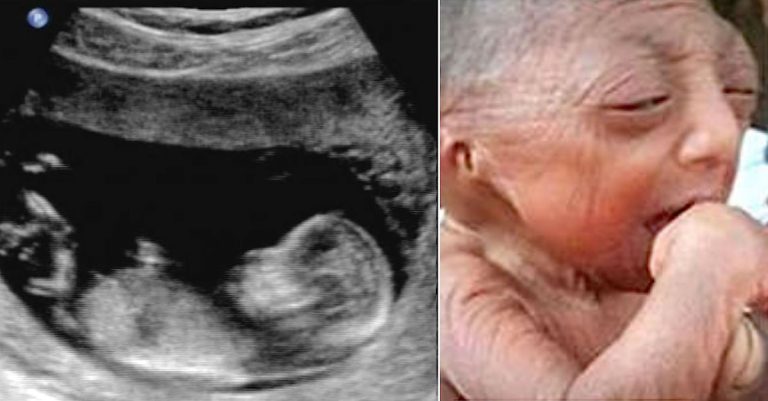

If you take a quick glance at Bayezid Hossain, you can tell that he’s been through a lot in life. Wisdom seeps from his eyes, and the wrinkles on his...